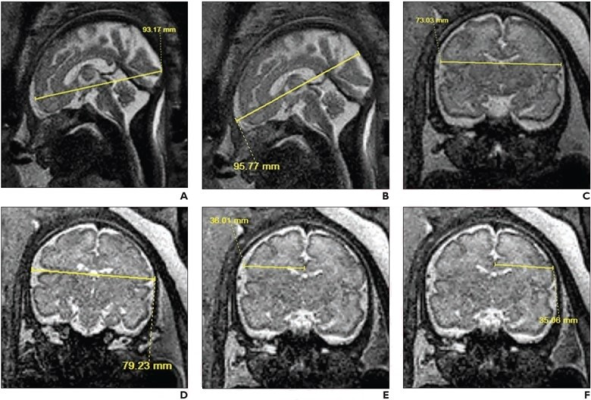

33-year-old patient (gestational age, 30 weeks and 6 days), without in utero opioid exposure, who underwent fetal MRI. Sagittal (A, B) and coronal (C-F) T2-weighted SSFSE images show 2D measurements of brain fronto-occipital diameter (A), bone fronto-occipital diameter (B), brain biparietal diameter (C), bone biparietal diameter (D), right cerebral biparietal diameter (E), left cerebral biparietal diameter (F).

Nagaraj and colleagues’ prospective multicenter case-control study included 65 women (mean age, 29 years) in their third trimester of pregnancy who underwent fetal MRI from July 1, 2020 through December 31, 2021 at three U.S. academic medical centers: Cincinnati Children’s Hospital Medical Center, Arkansas Children’s Hospital, and the University of North Carolina at Chapel Hill. A total of 28 fetuses (mean gestational age, 32.3 weeks) were classified as opioid-exposed, while 37 fetuses (mean gestational age, 31.9 weeks) were unexposed in utero. Fourteen 2D biometric measurements of the fetal brain were manually assessed and used to derive four indices.

When adjusting for gestational age, fetal sex, and nicotine exposure, 7 of the 14 2D biometric measurements—cerebral fronto-occipital diameter, bone biparietal diameter, brain biparietal diameter, corpus callosum length, vermis height, anterior-posterior pons measurement, and transverse cerebellar diameter—were significantly smaller in opioid-exposed fetuses than in unexposed fetuses, as measured on fetal MRI.